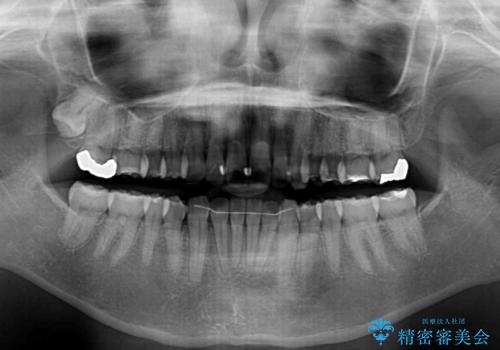

- 少しだけ前に飛び出ている前歯を気にして来院された患者様です。

上顎歯列全体を後方に移動させる必要があり、インビザライン単体での治療は困難と判断し、補助装置により左右側方歯列を移動させた後にインビザラインを用いることとしました。

インビザライン単独でも上顎歯列全体を後方移動することで臼歯の咬み合わせを改善できる場合もあります。しかしながら、矯正治療は当初設定したゴールに到達する必要があり、今回のような場合ではインビザライン単独では達成の可能性が低くなるので、補助装置を使用して、より確実に治療を行うこととしています。